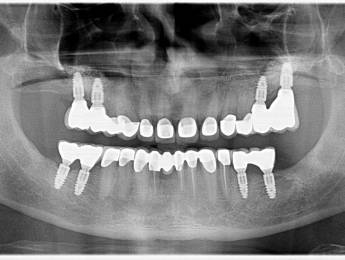

A páciens fogágybetegség miatt érkezett hozzánk. A felső fogak menthetetlen állapotban voltak. All on 6 megoldásként a felső fogak eltávolításakor 6 implantátum került beültetésre és a páciens azonnal egy fix ideiglenes hidat kapott. 4 hónapos gyógyulási idő után készült el a felső fémkerámia leplezésű körhíd.